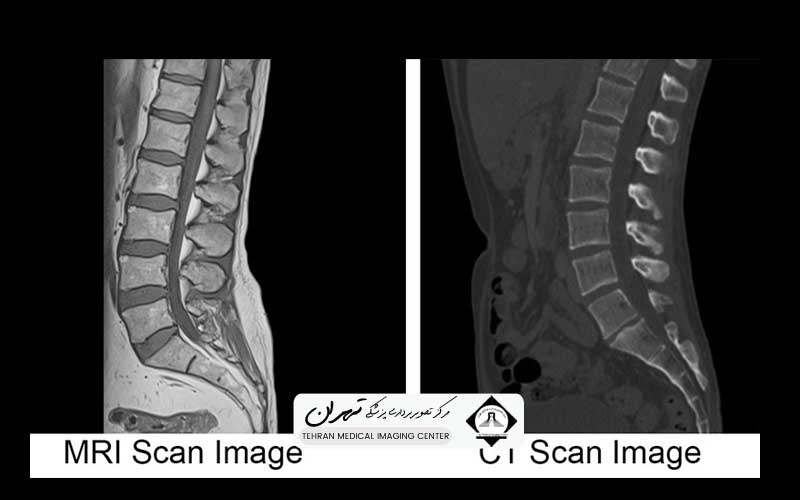

یکی از اساسیترین کاربردهای بالینی که فرق سی تی اسکن و ام آر آی را مشخص میکند، تفاوت در کنتراست و وضوح تصویر از بافتهای مختلف است. سی تی اسکن به دلیل اتکا به تراکم بافت (جذب اشعه ایکس)، در نمایش بافتهای سخت و متراکم مانند استخوانها و عروق خونی کلسیفیه شده، فوقالعاده عمل میکند. تصاویر سی تی اسکن برای تشخیص شکستگیها، ارزیابی ریه و تشخیص خونریزیهای حاد بسیار عالی هستند.

با این حال، سی تی اسکن در تمایز بین انواع مختلف بافتهای نرم (مانند تفاوت بین تومور و بافت مغزی نرمال) کنتراست پایینی دارد. به عبارت دیگر، بافتهای نرم با تراکم مشابه، رنگهای خاکستری یکسانی در تصویر سی تی اسکن پیدا میکنند و تشخیص مرز بین آنها دشوار میشود.

در نقطه مقابل، ام آر آی در تولید تصاویر با کنتراست عالی از بافتهای نرم بیرقیب است. به دلیل حساسیت بالا به محتوای آب و چربی بافتها، ام آر آی میتواند تفاوتهای ظریف در ترکیب شیمیایی بافتها را نشان دهد. این قابلیت باعث میشود که ام آر آی روش انتخابی برای تصویربرداری از سیستم عصبی مرکزی (مغز و نخاع)، مفاصل، رباطها، تاندونها و برخی تومورهای بافت نرم باشد.

به طور خلاصه، درک فرق سی تی اسکن و ام آر آی از منظر کیفیت تصویر به ما میگوید که برای دیدن ساختار استخوانی و ریه، سی تی اسکن و برای دیدن جزئیات بافت نرم و آسیبهای مغزی، ام آر آی ارجحیت دارد. پزشک با توجه به اندام مورد نظر، بهترین روش را برای دستیابی به اطلاعات تشخیصی با بالاترین وضوح انتخاب میکند.

در مقابل، ام آر آی به دلیل کنتراست عالی بافت نرم، معمولاً برای تشخیص شرایط غیر اورژانسی یا ارزیابیهای دقیقتر سیستم عصبی استفاده میشود. بیماریهایی مانند ام اس (MS)، تومورهای مغزی، سکتههای مغزی در مراحل اولیه، فتق دیسک در ستون فقرات، و آسیبهای رباط زانو و شانه، به بهترین شکل با ام آر آی تشخیص داده میشوند.

از دیدگاه متخصصان، فیلم و کیفیت نهایی تصاویر تولید شده توسط این دو دستگاه، جایی است که فرق سی تی اسکن و ام آر آی به طور واضح آشکار میشود. سی تی اسکن تصاویری تولید میکند که وضوح فضایی (Spatial Resolution) بسیار بالایی دارند و برای نمایش جزئیات کوچک استخوانی، گرههای ریوی و مرزهای هوایی عالی هستند.

فیلم سی تی اسکن، ساختارهای مختلف را عمدتاً در مقیاسهای خاکستری بر اساس چگالی نشان میدهد؛ استخوانها سفید روشن، بافت نرم طیفهای خاکستری و هوا سیاه است. با این حال، وضوح کنتراست (Contrast Resolution) آن برای تمایز بافتهای نرم مشابه، پایین است و این فرق سی تی اسکن و ام آر آی را در کیفیت خروجی نشان میدهد.

ام آر آی، تصاویری با وضوح کنتراست فوقالعاده بالا تولید میکند. فیلم ام آر آی میتواند تفاوتهای ظریف در محتوای آب و چربی بافتها را به صورت رنگهای خاکستری متفاوت نشان دهد، که این امر برای تشخیص پلاکهای کوچک در مغز (مانند بیماری ام اس) یا آسیبهای مینیسک زانو بسیار مهم است. تصاویر ام آر آی اغلب به چندین سکانس مختلف (مانند T1 و T2) تقسیم میشوند که هر کدام اطلاعات متفاوتی در مورد بافتها (مانند وجود آب، خون یا چربی) ارائه میدهند.

به طور خلاصه، برای یک متخصص، فرق سی تی اسکن و ام آر آی در نوع اطلاعاتی است که هر فیلم ارائه میدهد: سی تی اسکن بر ساختار سفت و تراکم متمرکز است، در حالی که ام آر آی بر ترکیب بافت نرم و تغییرات پاتولوژیک ظریفتر متمرکز است.